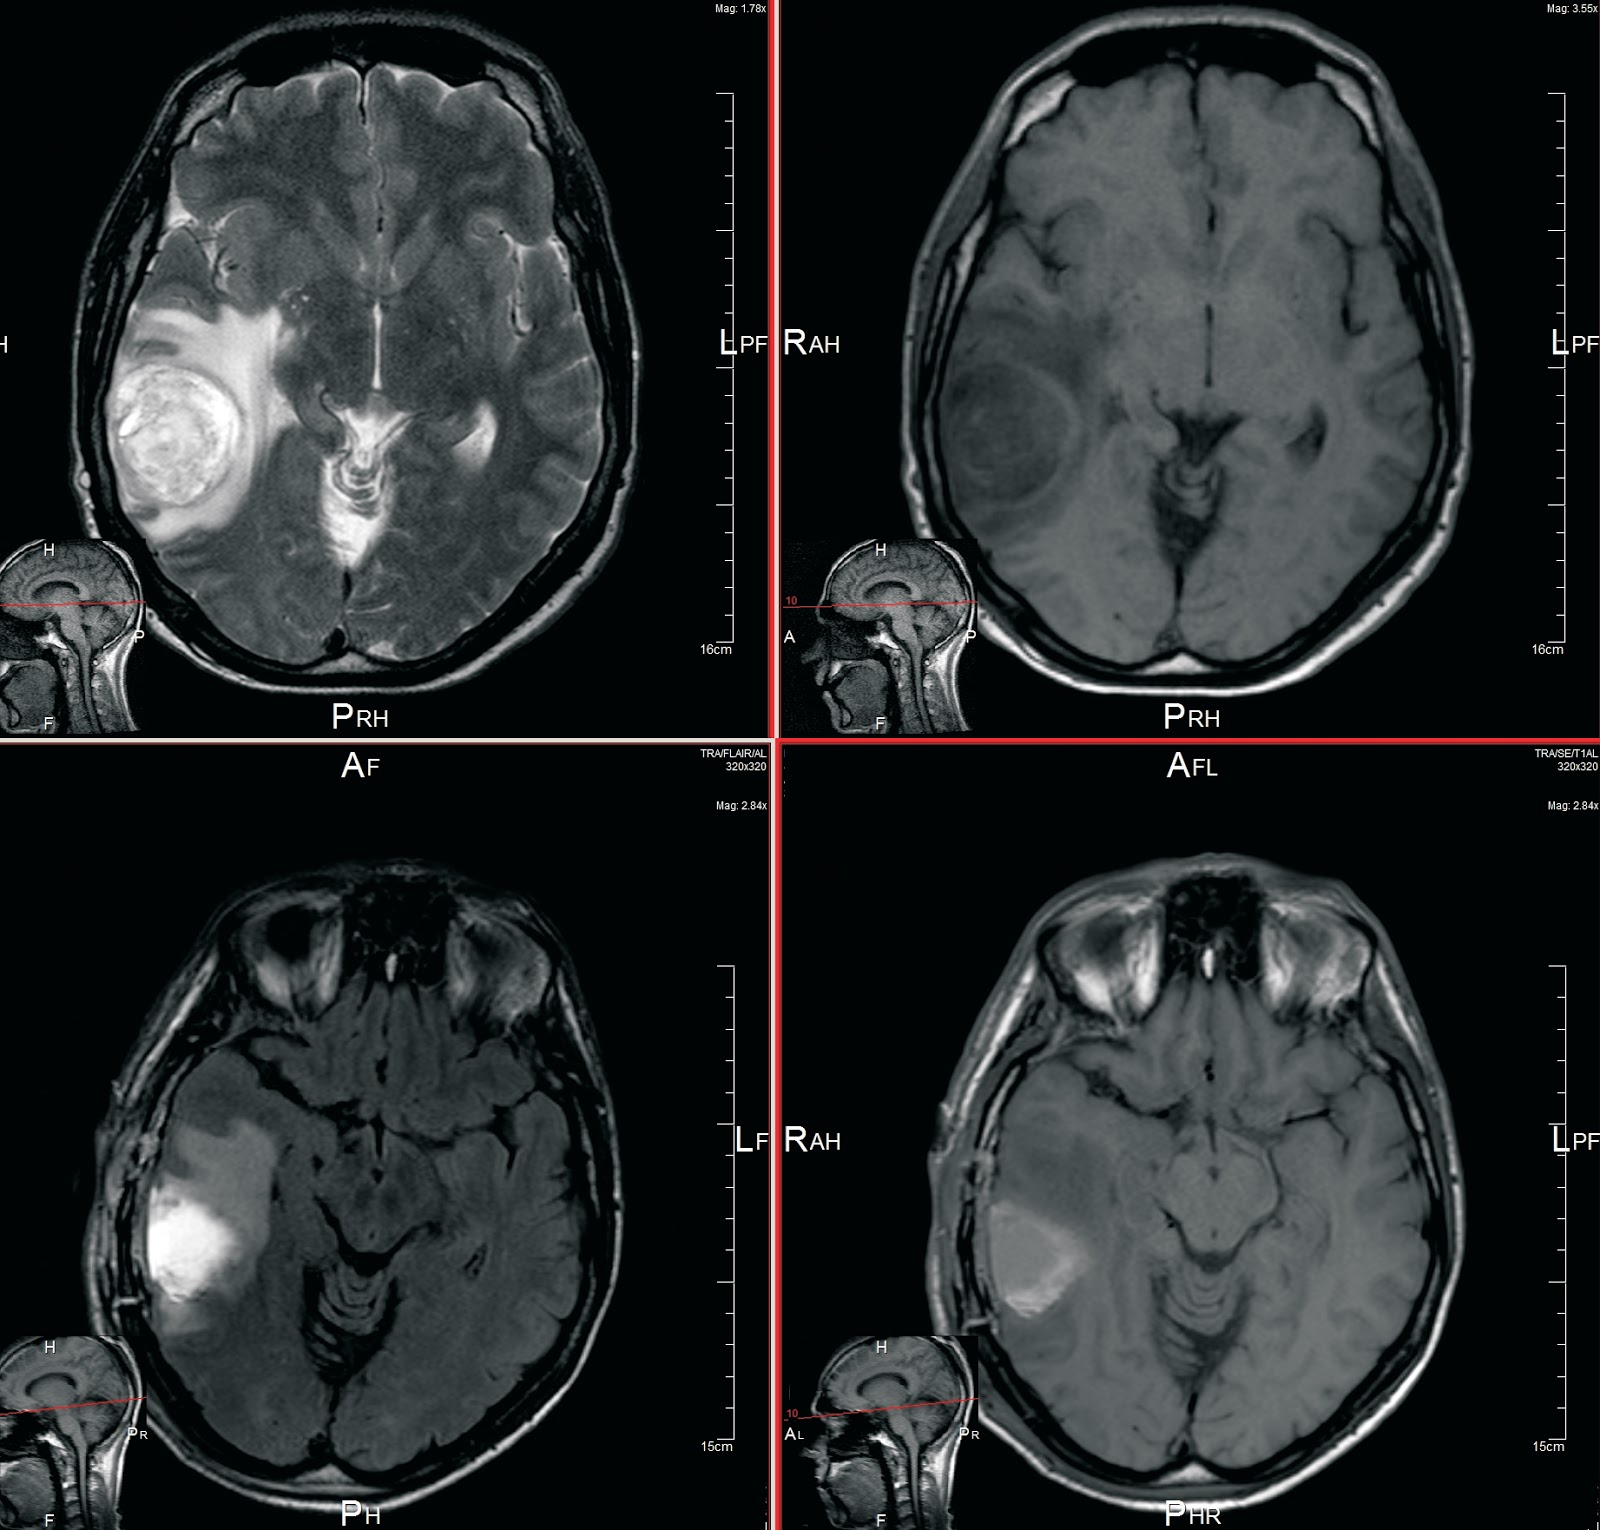

Glioblastoma multiforme 😈